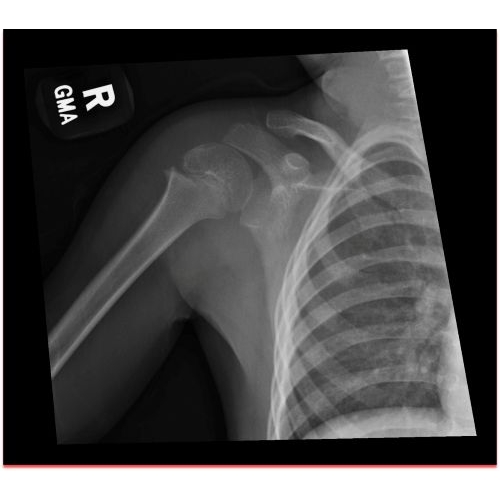

| Monkey Bar Mishap: A Unique Scapulothoracic Injury And Presentation - Page #3 | |||